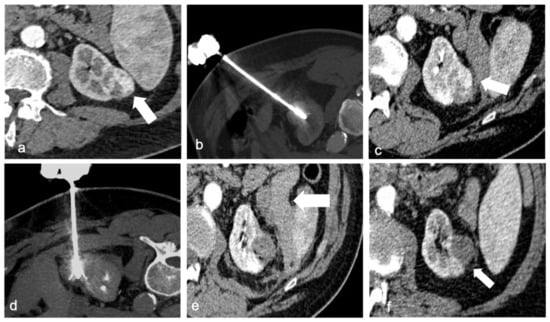

An important characteristic of RFA is the heat sink effect, generally known as a limit of this technique because the generated heat tends to decrease near structures with continuous liquid flow (large blood vessels ≥3 mm in diameter). This intrinsic feature can be useful to ablate perihilar tumors since it decreases the risk of damaging important anatomical structures with the high temperature. In addition, heat has an intrinsic coagulative effect, thus reducing the risk of minor hemorrhage [36]. Collecting system damage can occur as well, so it has been suggested placing a double J catheter in the ureter before the procedure in order to cool the collecting system (Figure 1). During the procedure, refrigerated water flows into the renal pelvis, protecting it from the heat [37].

Figure 1.

A 41-year-old woman with a biopsy-proven perihilar renal cell carcinoma of the right kidney ((a), arrow). Ureteral double-J stent was positioned right before the procedure to protect the pelvis and urinary tract with continuous refrigerated water flow (b). Precise positioning of the multi-tined RF probe in the right renal hilum mass (c). Contrast-enhanced CT after ablation shows the necrotic area (arrow), without any residual disease or immediate complication (d).

The technical success rate for ablations of T1a (≤4 cm) lesions is close to 100%, and the primary local control is excellent (Figure 2). The outcomes of T1a lesions treated with RF, CA, or MW ablation were comparable to those of total or partial nephrectomy (5-year cancer-specific survival 95–98%), but there were fewer post-procedural complications, unplanned hospital readmissions, decreased 30- and 90-day mortality, and a lower risk of long-term renal insufficiency [52].

Figure 2.

A 67-year-old man with a 34 mm renal cell carcinoma in the left kidney. Axial contrast-enhanced CT (a) demonstrates a heterogeneously enhancing mass (arrow). RF ablation was performed with multitined expandable electrods (b), but post-procedural contrast-enhanced CT revealed areas of enhancement in the mass (arrow) compatible with residual disease (c). A second target positioning was performed to achieve a complete ablation (d). Post-procedural CT shows no enhancement of the ablated lesion and a small hematoma (arrow, (e)). Follow-up CT after 4 weeks revealed no evidence of residual or recurrent disease (arrow) and partial reabsorption of the hematoma (f).